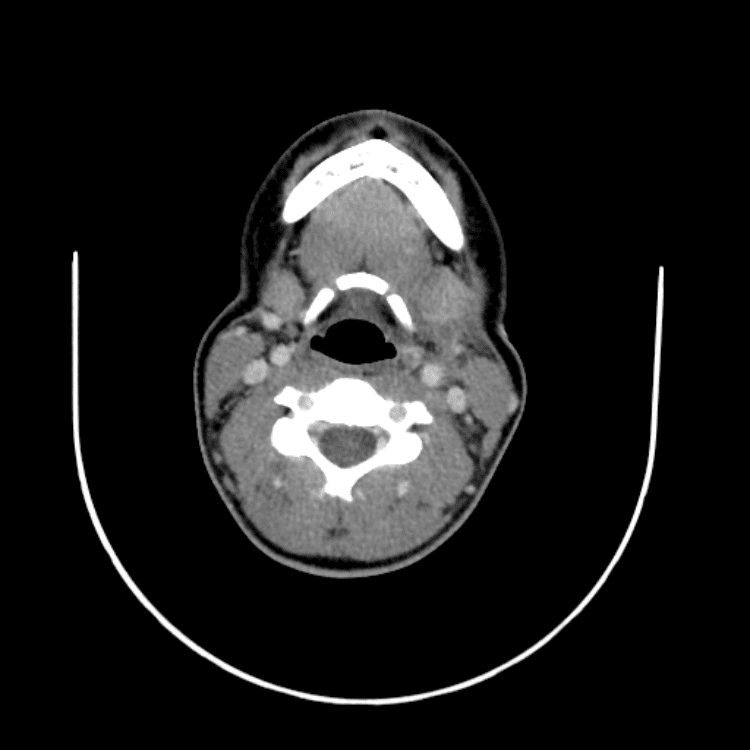

Head and Neck

Simulates call by including subtle or difficult cases and some normals.

27 cases